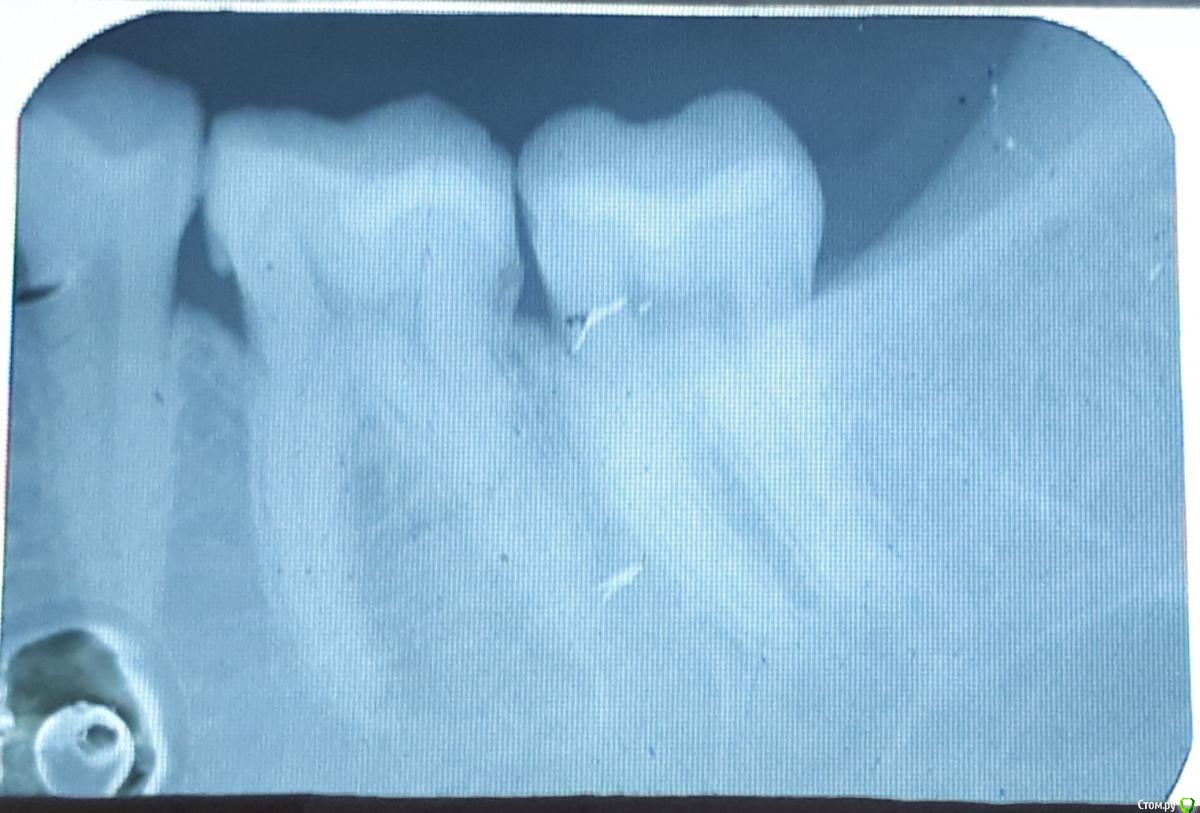

Яковлева Ксения Опубликовано 28 июля, 2019 Поделиться Опубликовано 28 июля, 2019 (изменено) Здравствуйте, уважаемые врачи! 3 недели назад мне запломбировали глубокий кариес в 6 и 7 нижних зубах с правой стороны. До этого эти зубы не беспокоили и не болели. И вот уже 3 недели меня беспокоют ноющие боли. Болит как в течение дня, так и вечером. Когда ем, то твердую пищу больно пережевывать этой стороной, Но болит терпимо. Стоматолог, который пломбировал, считает что так реагирует именно 7 зуб. Он также чувствителен на холодную пищу, на горячее не реагирует. Пломбу уже дважды подпиливали по прикусу, покрывали специальным составом для снижения чувствительности. Я также принимала нимесил в течение 5 дней по рекомендации врача для снижения боли и чистила зубы Сендодином. По рентгену стоматолог сказал, что все хорошо, но если будет и дальше так зуб беспокоить, то стоит его депульпировать (рентген прилагаю). 27.07.2019 я пошла в частную поликлинику, где мне сделали прицельную компьютерную томографию, которая показала, что пломбы как бы не плотно прилегают к зубу. Стоматолог в частной клинике предложил перелечить пломбы. После приема вечером правая сторона разболелась сама по себе, отдавая то в верхнюю челюсть, то под нижнюю челюсть, то в область уха. Болел где-то с 23:30 до 01:30 ночи. Имеет ли смысл перелечивать пломбы на причинных зубах или это пульпит и стоит просто депульпировать 7 зуб? И если перелечивать, не рассверлят ли мне еще глубже полости когда будут снимать пломбы и не приведет ли это к пульпиту? Буду очень признательна вам за консультацию. Фотографии проекций КТ прилагаю. Стрелочками карандашом показаны проблемные места на зубах. Изменено 28 июля, 2019 пользователем Яковлева Ксения Ссылка на комментарий